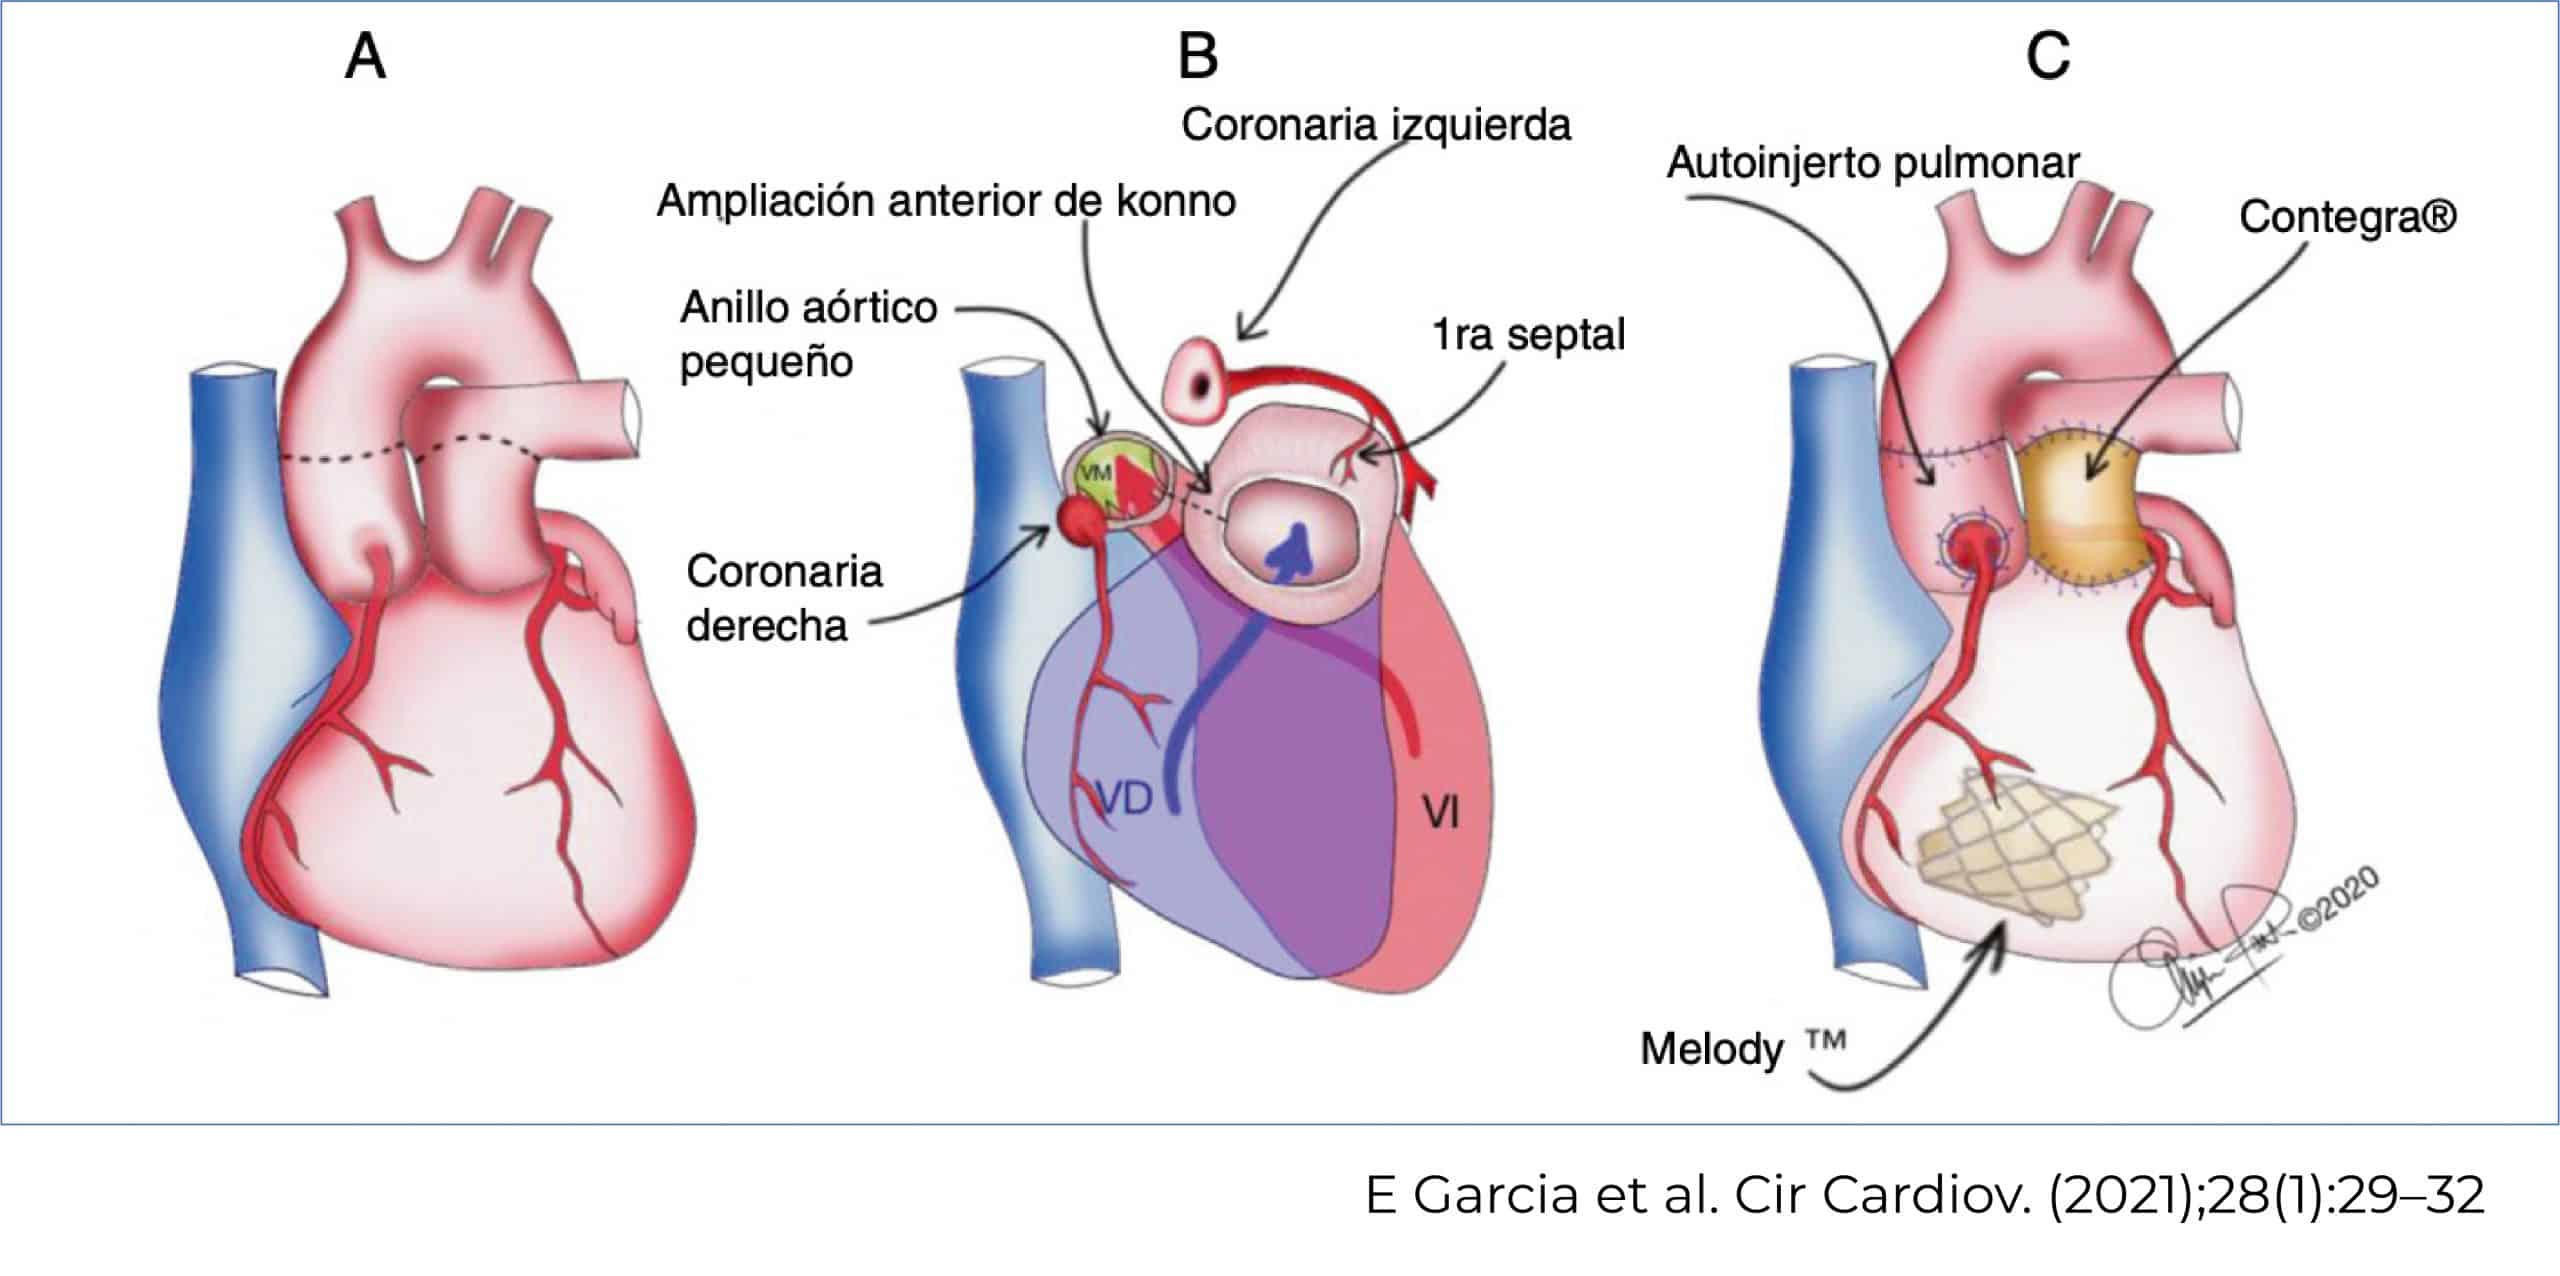

Cirugía de Ross-Konno

La cirugía de Ross-Konno permite reparar la válvula aórtica dañada. Para ello, se utiliza la válvula pulmonar en posición aortica con translocación de las coronarias y en posición pulmonar se colocó un conducto contegra.

Además, debido a la doble lesión mitral con insuficiencia grave, también se colocó una válvula Melody® en posición mitral; y se realizó una resección de fibroelastosis.